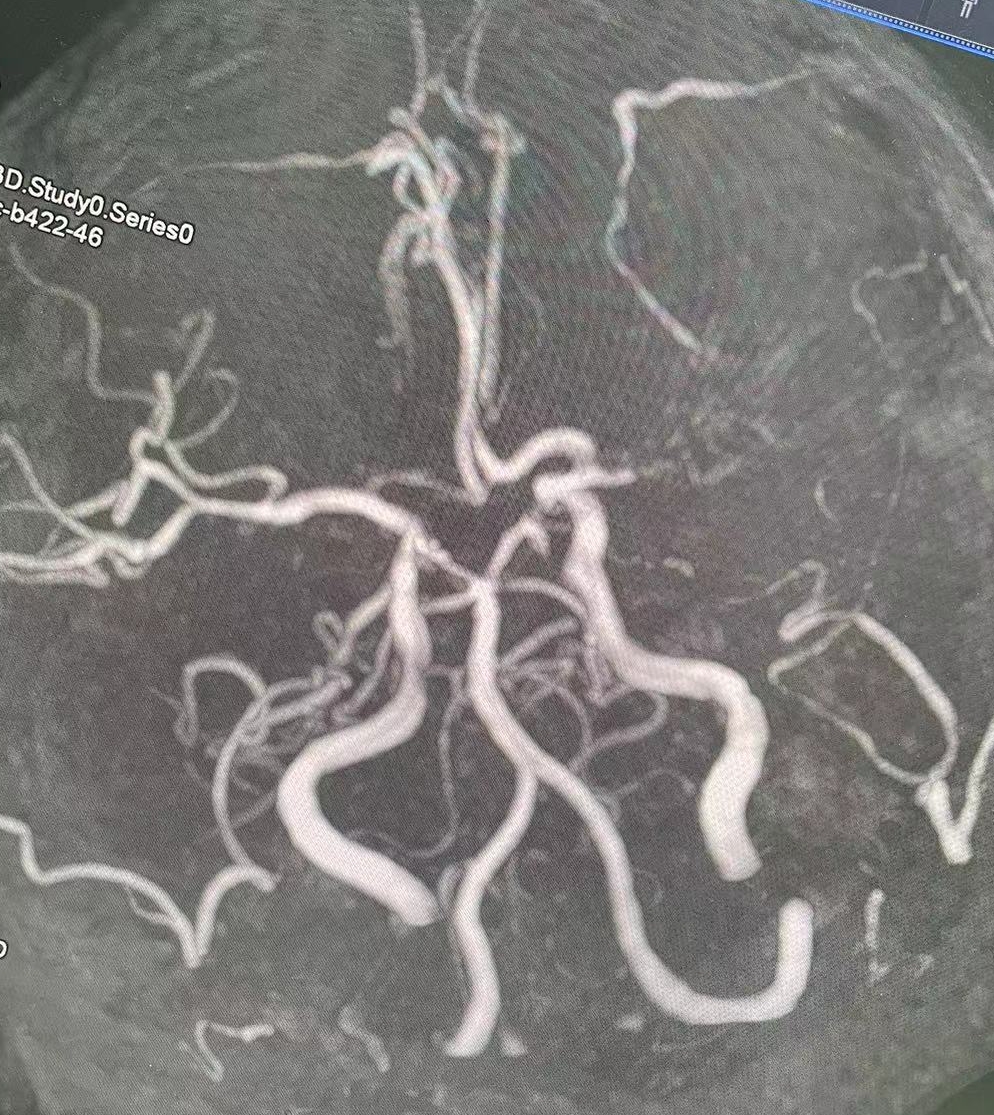

1、本例患者老年女性,系骨科术后次日醒后卒中,经核磁评估提示左侧大脑中动脉闭塞,系责任血管,患者心电图示房颤,考虑心源性栓塞可能性大。

2、本例患者SWIM技术取栓一次后血管再通,颅内血流通畅。